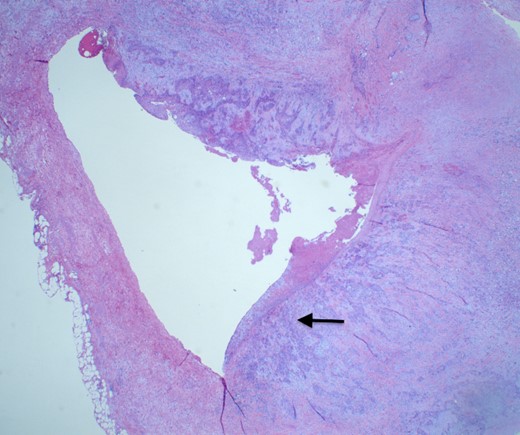

She underwent an open pylorus-preserving pancreatoduodenectomy with segmental superior mesenteric vein resection with primary reconstruction (ISGPS Type 3) without complication. Final pathology demonstrated a 3.6-cm poorly differentiated adenosquamous carcinoma with SMV invasion into the intima (Fig. 2), 1 of 24 regional lymph nodes with metastatic carcinoma, lymphovascular and perineural invasion (Fig. 3), and an 85% squamous differentiation (Fig. 4). There was a partial pathologic response (College of American Pathologist Grade 2) within the primary tumor and involved lymph node tumor [7]. There was noted to be tumor extension within 1 mm of the superior mesenteric artery margin (Fig. 5) (R1 status) with negative additional margins. She recovered without complications and was discharged home on the fourth post-operative day. Repeat staging CT imaging demonstrated no evident disease. She was initiated on adjuvant systemic therapy.